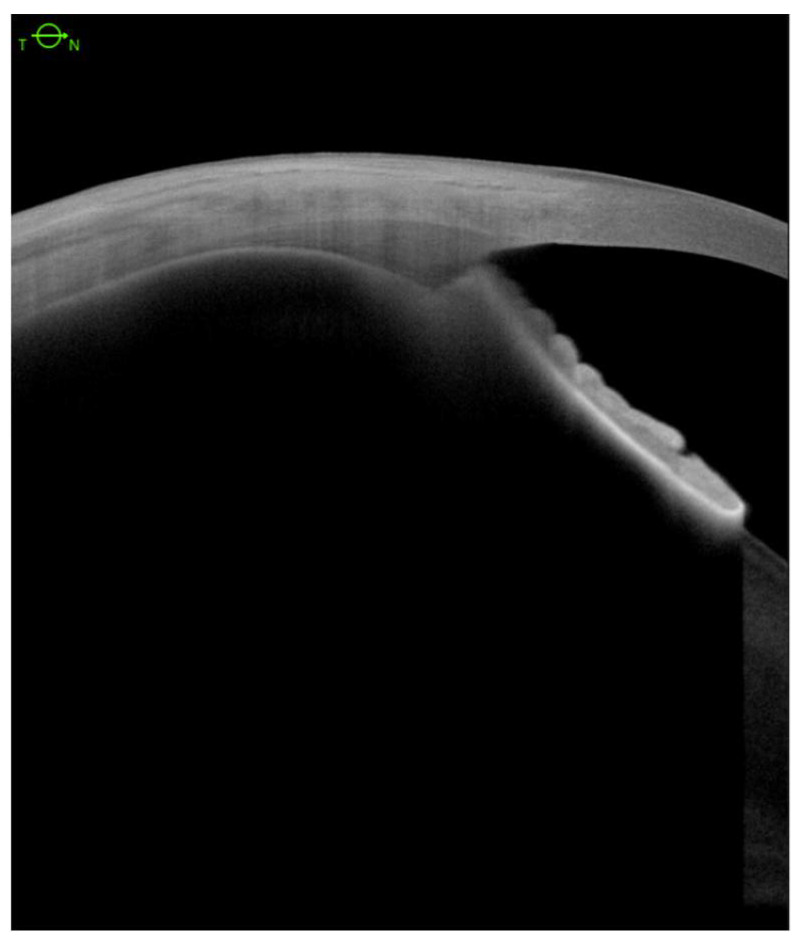

Ciliary body structures in patients were analyzed with severe hypotony following multiple surgeries to correct retinal detachment. Anatomical outcomes were assessed using AS-SS-OCT images (Figure 1).

Ciliary body detachment (CBD) secondary to the advanced cyclitic membrane associated with PVR grades C and D was detected in all eyes with hypotony (Table 1). We defined three patterns of CBD: (1) detachment between the longitudinal, circular, and oblique fibers (Figure 2a); (2) complete detachment with supraciliary fluid of varying thicknesses in all 4 quadrants (Figure 2b); (3) detachment in the pars plicata (Figure 2c).

We analyzed CBD before and after scleral buckling surgery (Figure 3a,b), and no eye showed any significant changes postoperatively (Figure 3c,d).